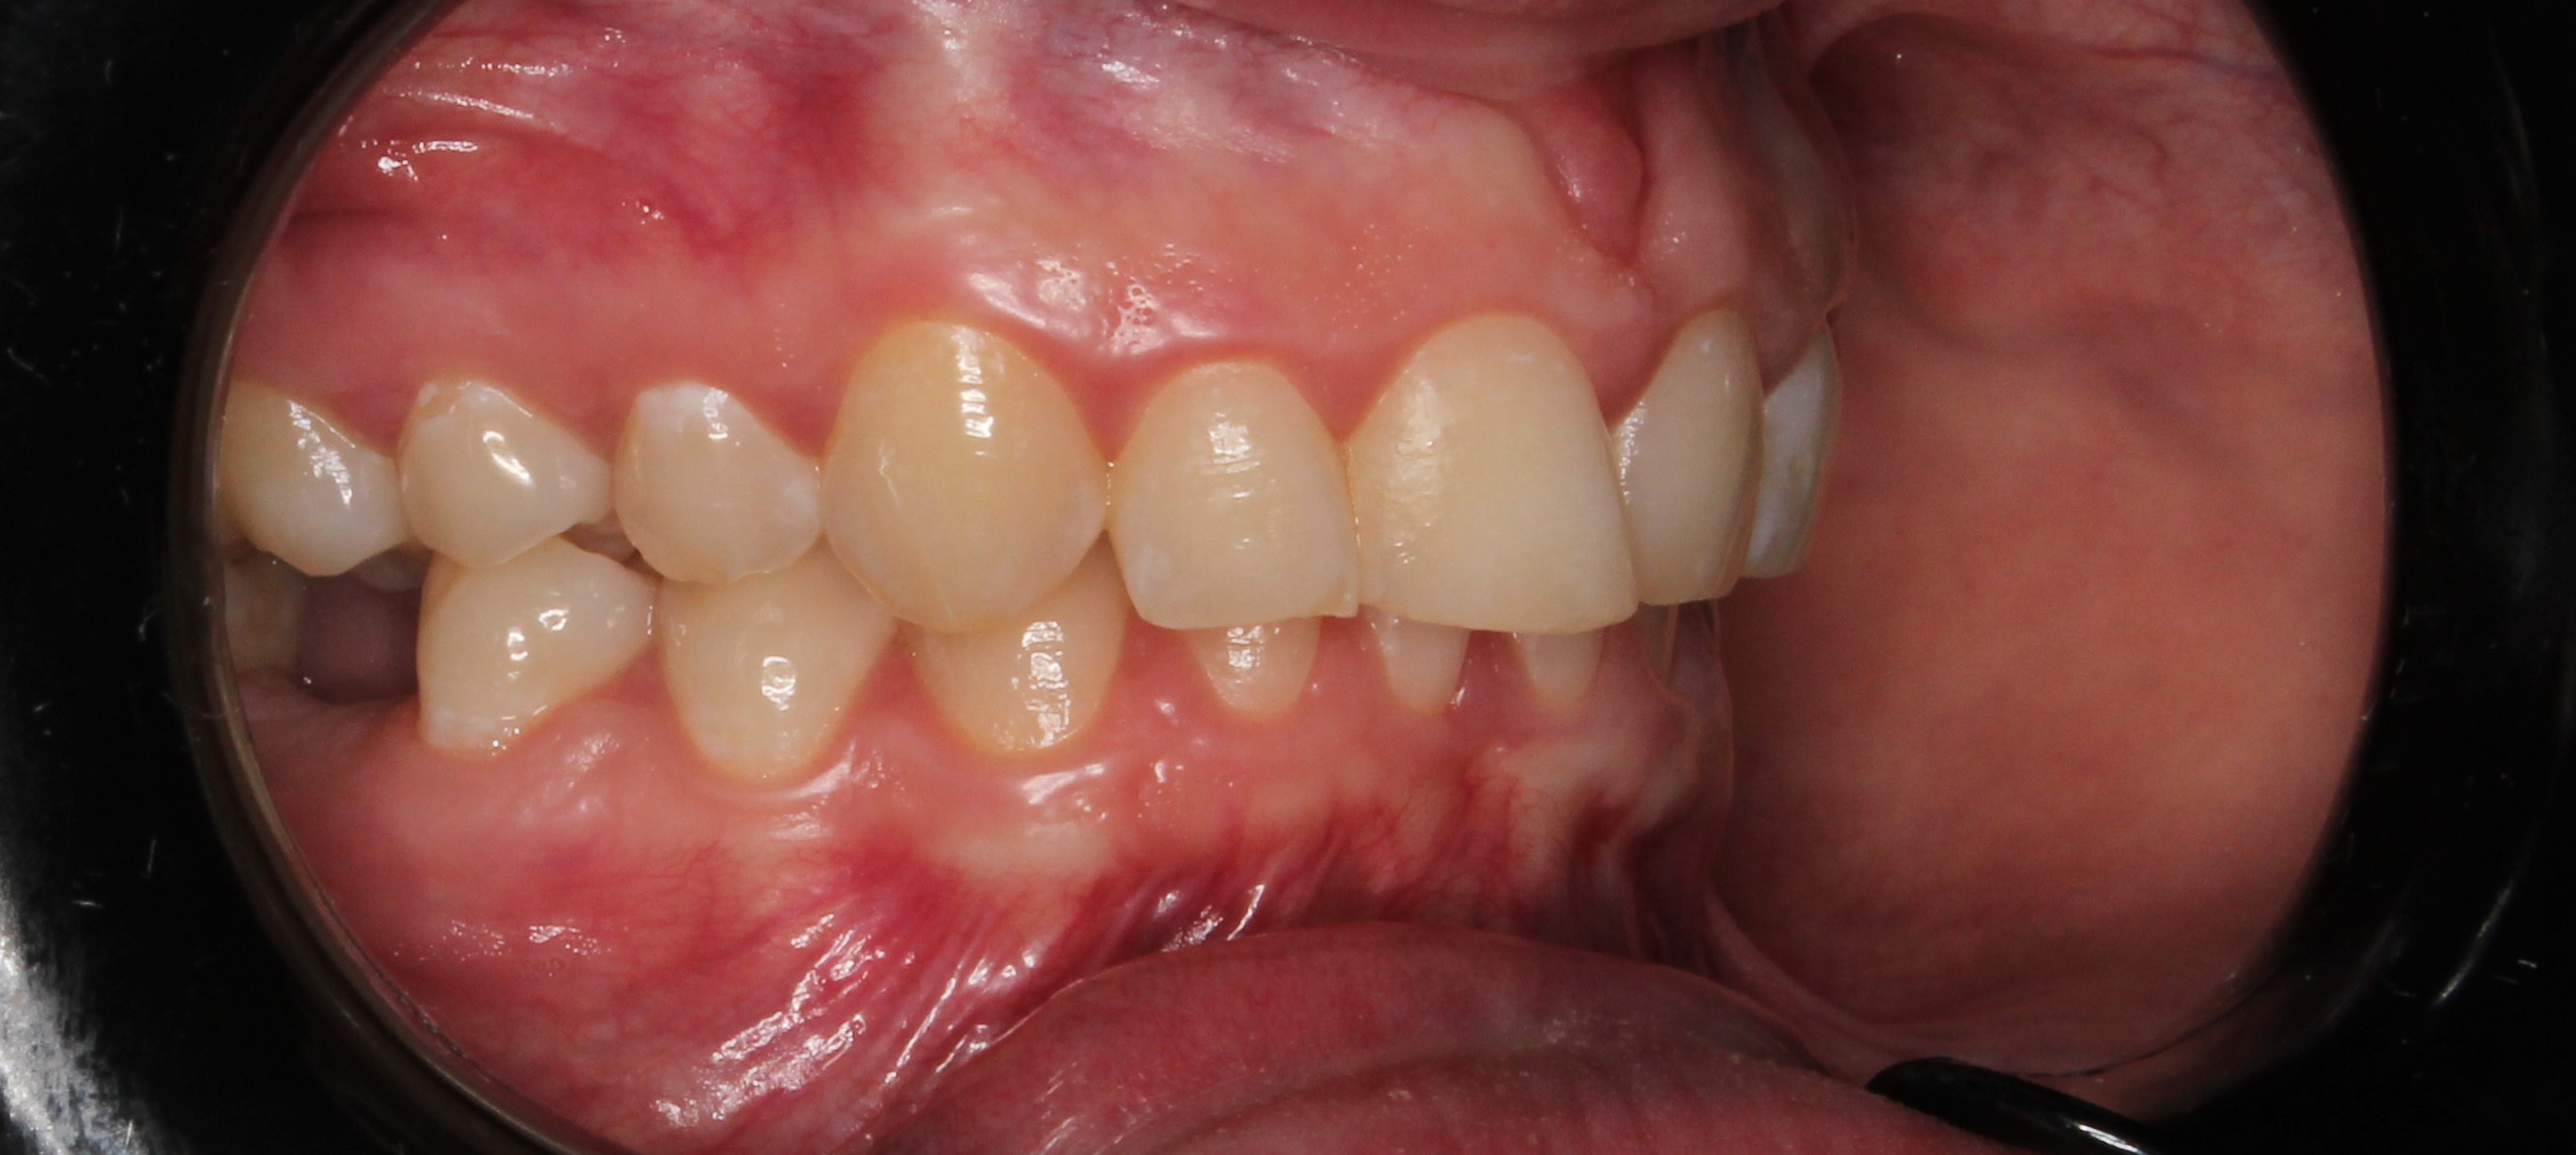

До и После: Лечение глубокого прикуса элайнерами

Лечение глубокого прикуса элайнерами. Начало лечения. Фиксация элайнеров